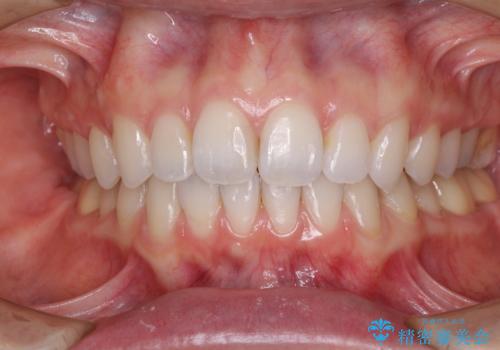

深い咬み合わせと奥歯のむし歯 総合歯科治療

矯正治療後は、奥歯の虫歯や銀歯を補綴・修復治療することとしました。

上顎歯列を下顎に対して4mmほど移動させる必要があったため、治療は長期化することが予想されましたが、患者様にはこちらの期待以上にゴムかけなどに協力いただき、補綴治療も含めて2年強で終えることができました。